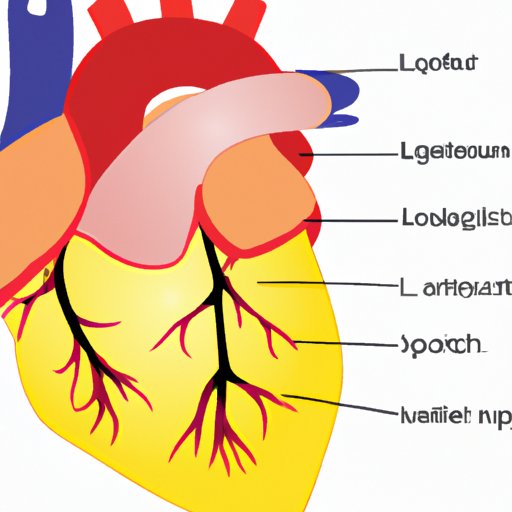

The Heart Side | Understanding the Placement and Importance of the Heart in Human Anatomy

Discover the placement and importance of the heart in human anatomy. This guide explores common myths, facts, and cultural significance of knowing the left or right side of the heart to promote a better understanding of overall health and well-being.

Exploring Which Cavity Contains the Heart: An Anatomy Guide

Understanding the location of the heart in the body and the cavity that houses it is critical for understanding its vital role. This article provides an overview of the thoracic cavity and the pericardial cavity, highlighting the importance of their structures in supporting and protecting the heart.

The Four Chambers of the Heart: Anatomy, Function, and Evolution

This article explores the anatomy and function of the heart’s chambers, the evolution of heart chambers in different species, and other fascinating aspects of the human heart. From myths about the heart to congenital heart defects, this article is a comprehensive overview of an essential organ in our body.